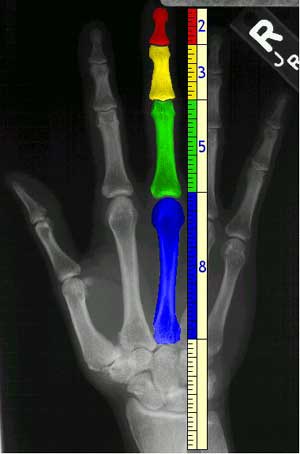

Los patrones de crecimiento de las plantas se replican en nuestro propio cuerpo.

No olvidemos que las palabras "tronco" y "axila" (punto en que se une una rama al tronco por la parte que forma ángulo agudo) aluden al reino vegetal.

( Img: //www.eatonhand.com/hw/fibonacci1.jpg)